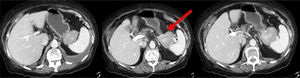

Mujer de 78 años con alergia a antiinflamatorios no esteroideos y antecedentes de hipertensión arterial, diabetes mellitus tipo 2 y fibrilación auricular. Consulta por dolor abdominal creciente de 3 meses de evolución localizado en epigastrio e hipocondrio izquierdo, que no cede con analgesia habitual, asociando anorexia, náuseas, vómitos y pérdida de peso de 4kg. Analítica sin alteraciones relevantes. La TC toracoabdominal muestra, como único hallazgo, una lesión de 60mm sólida y vascularizada en fase portal, entre curvatura mayor gástrica e hilio esplénico, al que desplaza sin infiltrar. La lesión presenta pequeñas adenopatías satélites y pericelíacas. Los hallazgos indican un posible tumor estromal (GIST) sin descartar dependencia del páncreas (fig. 1). Se realiza punción ecoendoscópica, evidenciándose tejido linfoide con agregados de histiocitos epiteliodes, CD68+ y marcadores GIST negativos (reacción inflamatoria crónica con granulomas histiocitarios no caseificantes). Ante la duda diagnóstica, la clínica de la paciente y la imposibilidad de descartar malignidad se decide intervención tras presentar el caso en comité multidisciplinar, accediéndose mediante abordaje laparoscópico y convirtiendo a laparotomía subcostal bilateral por inestabilidad hemodinámica y episodios de taquicardia ventricular sostenida, objetivándose un infiltrado difuso granulomatoso retroperitoneal y ascitis de 3,5l. Se toman biopsias intraoperatorias peritoneales negativas para malignidad, informadas como tejido fibroconectivo con inflamación crónica, linfoide y presencia de granulomas con células gigantes multinucleadas. Se realiza pancreatectomía corporocaudal y esplenectomía. Postoperatorio en UCI precisando fármacos vasoactivos y perfusión de amiodarona por episodio de fibrilación auricular. Evolución favorable siendo alta a planta al tercer día postoperatorio y domiciliaria al séptimo día sin más incidencias (Clavien-Dindo IVa). La histología mostró una tumoración lisa de 60×50mm, dependiente del páncreas y con foco de calcificación intratumoral. Microscópicamente se observan ganglios linfáticos peripancreáticos con granulomas ricos en células epitelioides, células gigantes multinucleadas e inflamación crónica sin necrosis. La morfología de la lesión indica sarcoidosis (fig. 2). La ampliación diagnóstica del estudio histoquímico de bacilos ácido-alcohol resistentes (Ziehl-Neelsen y Fite-Faraco), fueron ambos negativos, confirmando el diagnóstico final de sarcoidosis. Seguimiento posterior en consulta favorable, sin complicaciones quirúrgicas ni endocrinometabólicas.